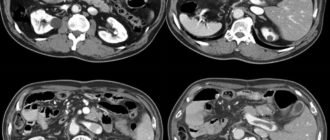

Мультилокулярная киста почки

Кисты почек Киста почки – это округлое, жидкостное образование почки, которое считается доброкачественным. Кистозное